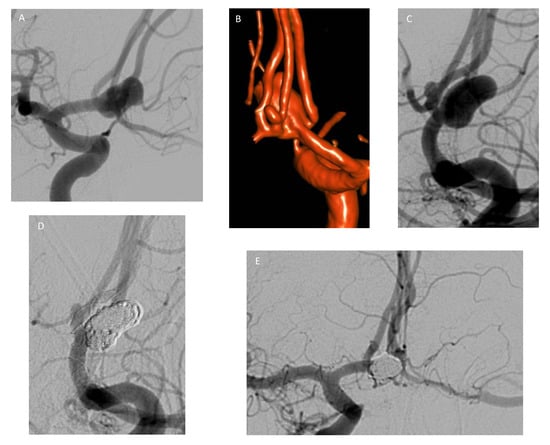

3.5. Flow Diversion

- Lubicz, B.; Collignon, L.; Raphaeli, G.; Pruvo, J.P.; Bruneau, M.; De Witte, O.; Leclerc, X. Flow-Diverter Stent for the Endovascular Treatment of Intracranial Aneurysms: A Prospective Study in 29 Patients with 34 Aneurysms. Stroke 2010, 41, 2247–2253. [Google Scholar] [CrossRef] [PubMed]

- Lylyk, P.; Miranda, C.; Ceratto, R.; Ferrario, A.; Scrivano, E.; Luna, H.R.; Berez, A.L.; Tran, Q.; Nelson, P.K.; Fiorella, D. Curative Endovascular Reconstruction of Cerebral Aneurysms with the Pipeline Embolization Device: The Buenos Aires Experience. Neurosurgery 2009, 64, 632–642. [Google Scholar] [CrossRef]

- Szikora, I.; Berentei, Z.; Kulcsar, Z.; Marosfoi, M.; Vajda, Z.S.; Lee, W.; Berez, A.; Nelson, P.K. Treatment of Intracranial Aneurysms by Functional Reconstruction of the Parent Artery: The Budapest Experience with the Pipeline Embolization Device. Am. J. Neuroradiol. 2010, 31, 1139–1147. [Google Scholar] [CrossRef]

- Nelson, P.K.; Lylyk, P.; Szikora, I.; Wetzel, S.G.; Wanke, I.; Fiorella, D. The Pipeline Embolization Device for the Intracranial Treatment of Aneurysms Trial. Am. J. Neuroradiol. 2011, 32, 34–40. [Google Scholar] [CrossRef] [PubMed]

- Becske, T.; Kallmes, D.F.; Saatci, I.; McDougall, C.G.; Szikora, I.; Lanzino, G.; Moran, C.J.; Woo, H.H.; Lopes, D.K.; Berez, A.L.; et al. Pipeline for Uncoilable or Failed Aneurysms: Results from a Multicenter Clinical Trial. Radiology 2013, 267, 858–868. [Google Scholar] [CrossRef]